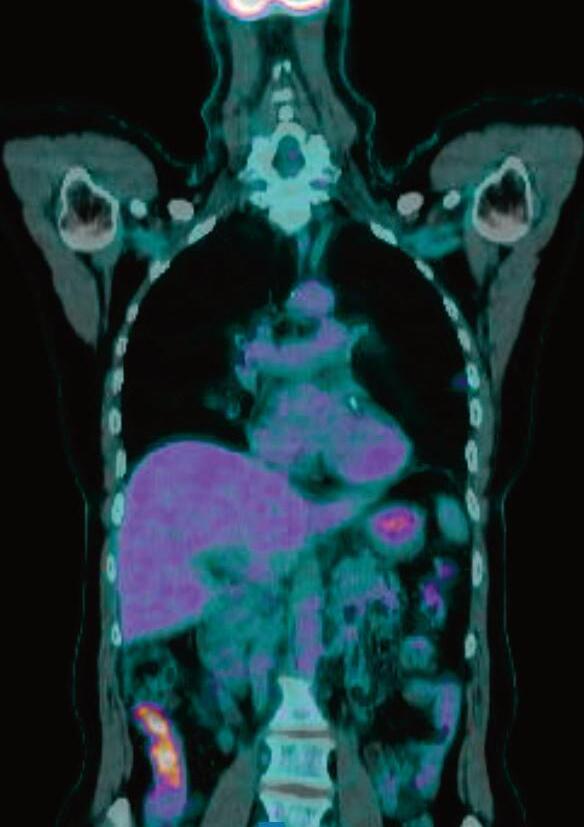

NUOVE FRONTIERE PER IL TRATTAMENTO DEL CANCRO TIROIDEO AVANZATO: STRATEGIE INNOVATIVE DI REDIFFERENZIAZIONE

Livia Lamartina, Desiree Deandreis